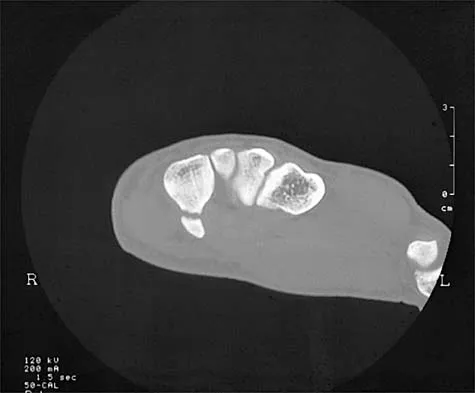

A 14-year-old boy reports pain in the distal thigh. He denies any history of trauma. Examination reveals tenderness and swelling of the distal thigh without effusion. A radiograph and CT scan are shown in Figures 10a and 10b. A biopsy specimen is shown in Figure 10c. Management should consist of

Based on these findings, the patient has an aneurysmal bone cyst. Frequently, fluid-fluid levels can be detected on MRI or CT images. The histologic results show a lesion that consists of cavernous spaces filled with blood. The lining of the cavity contains spindle cells, multinucleated giant cells, and reactive bone. Curettage and bone grafting is the preferred treatment method. Without treatment, these lesions can become quite large and destructive. Radiation therapy is not recommended for resectable lesions. Chemotherapy is not required for these benign lesions. Simon MA, Springfield DS, et al: Common Benign Bone Tumors: Surgery for Bone and Soft Tissue Tumors. Philadelphia, PA, Lippincott Raven, 1998, pp 194-200.